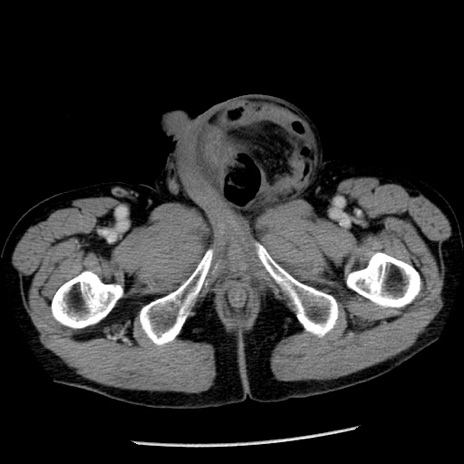

冠状断像

症例26(横断像)

【症例】80歳代男性

【主訴】嘔吐

【現病歴】昨晩2回嘔吐あり、今朝になっても嘔吐あり。来院。

【既往歴】胃潰瘍

【身体所見】意識清明、BT 37.6℃、BP 166/95mmHg、HR 100bpm、SpO2 97%、腹部:平坦・軟、腸蠕動音聴取良好、圧痛なし。

【データ】WBC 21900、CRP 1.46